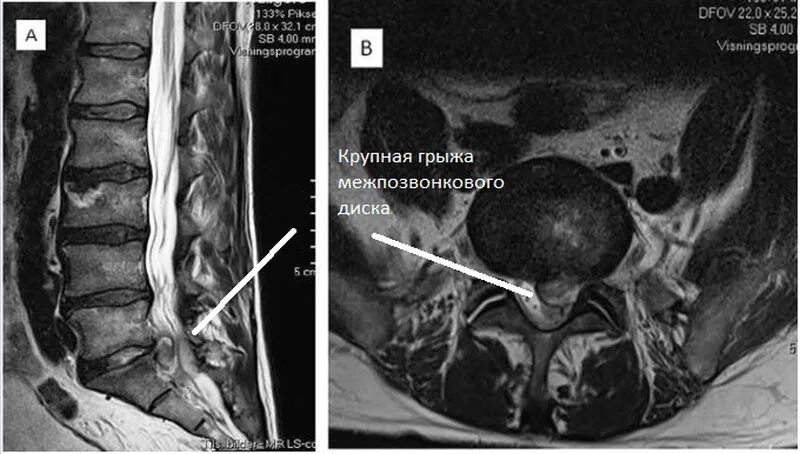

Что можно увидеть на мрт